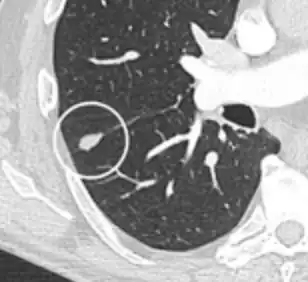

- Margin morphology: a spiculated margin is a risk factor for cancer.[8] Benign causes tend to have a well defined border, whereas lobulated lesions or those with an irregular margin extending into the neighbouring tissue tend to be malignant.[10] In particular, spiculations are highly predictive of malignancy with a positive predictive value up to 90%.[9] Also, a "notch sign", which is an abrupt indentation of the nodule, increases the risk of cancer, but may also be found in granulomatous diseases.[9]

subpleural nodule.[9]

Round well-delineated solid lung nodule with smooth border.[9]